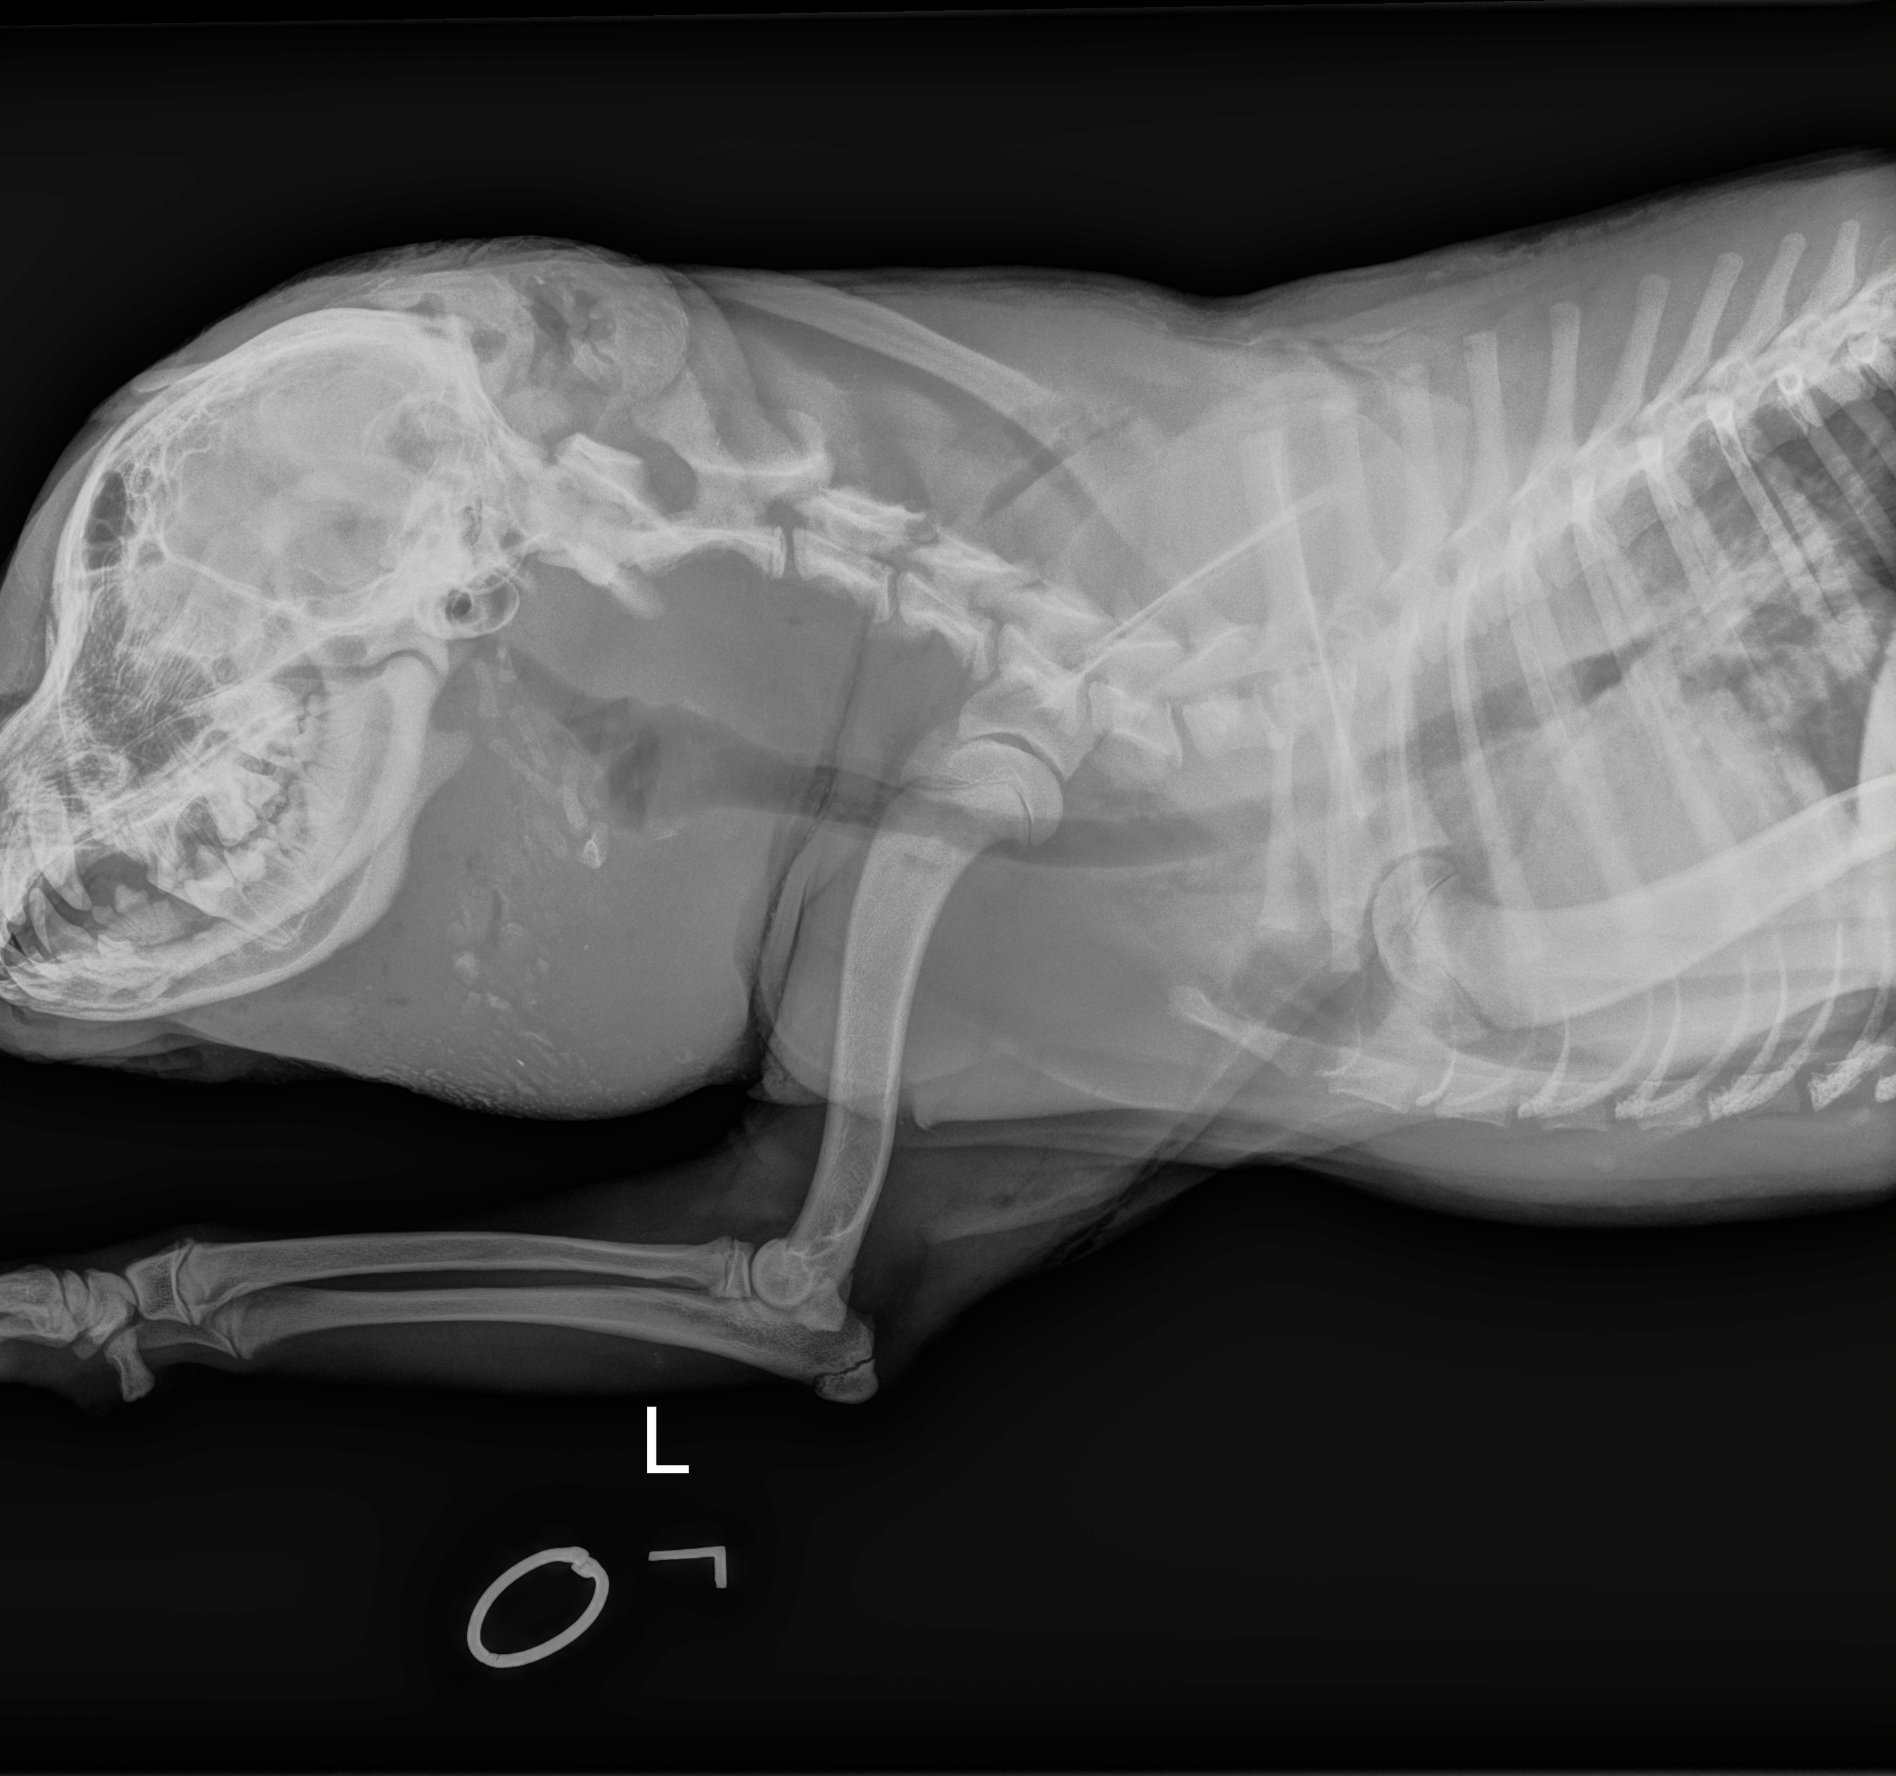

Once Jessie was sedated and her wounds were cleaned, the true extent of her trauma was revealed through the cold, gray lens of an X-ray.

The findings were shocking. The orbital bone—the structure right below her eye—was completely shattered. Her teeth on the same side were a mess of broken enamel and roots. While the majority of the trauma was concentrated on one side of her face, wounds were also found hidden behind her ears and on top of her head.

It remained a mystery. There were no bullet holes, and while they looked like bite wounds, there wasn’t a single scratch on her legs or body. It was as if someone—or something—had targeted only her head. Despite the low blood cell counts and the severe infection, her doctors remained focused. Jessie was finally in the right hands.